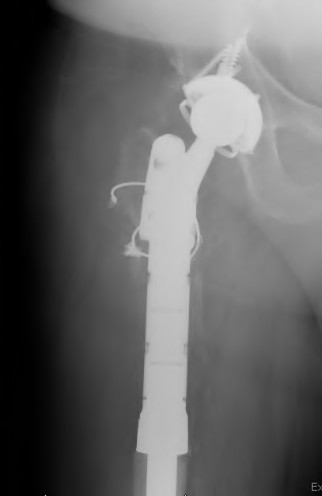

Question 51

A patient requires a femoral revision THA for aseptic loosening. Radiographs demonstrate extensive metaphyseal bone loss with the diaphyseal cortical bone remaining fully intact for only 3 cm distal to the tip of the current stem. According to the Paprosky femoral defect classification, what type of defect is present?